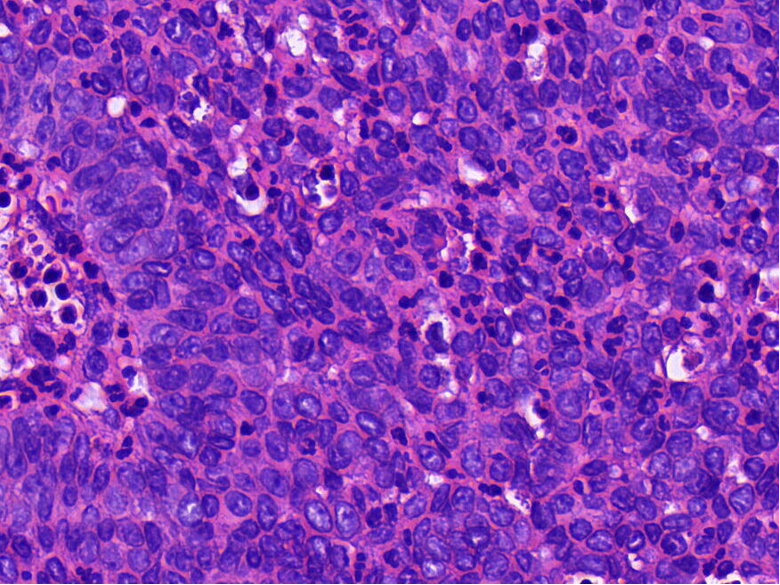

病理特征:宽薄乳头、 迷宫样内翻生长、单一肿瘤细胞形态、棘层松解、显著中性粒细胞浸润;

可见:细胞旋涡、透明细胞变、微囊形成、黏液纤毛上皮帽、部分肿瘤细胞异型性增加、坏死。

具有纤毛上皮帽